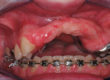

Quel auxiliaire pour la disjonction/ distraction en technique linguale

Dr A. MARINETTI

Spécialiste qualifié en ODF

Exercice privé, Paris

Ancien président de la Société Française d’Orthodontie Linguale